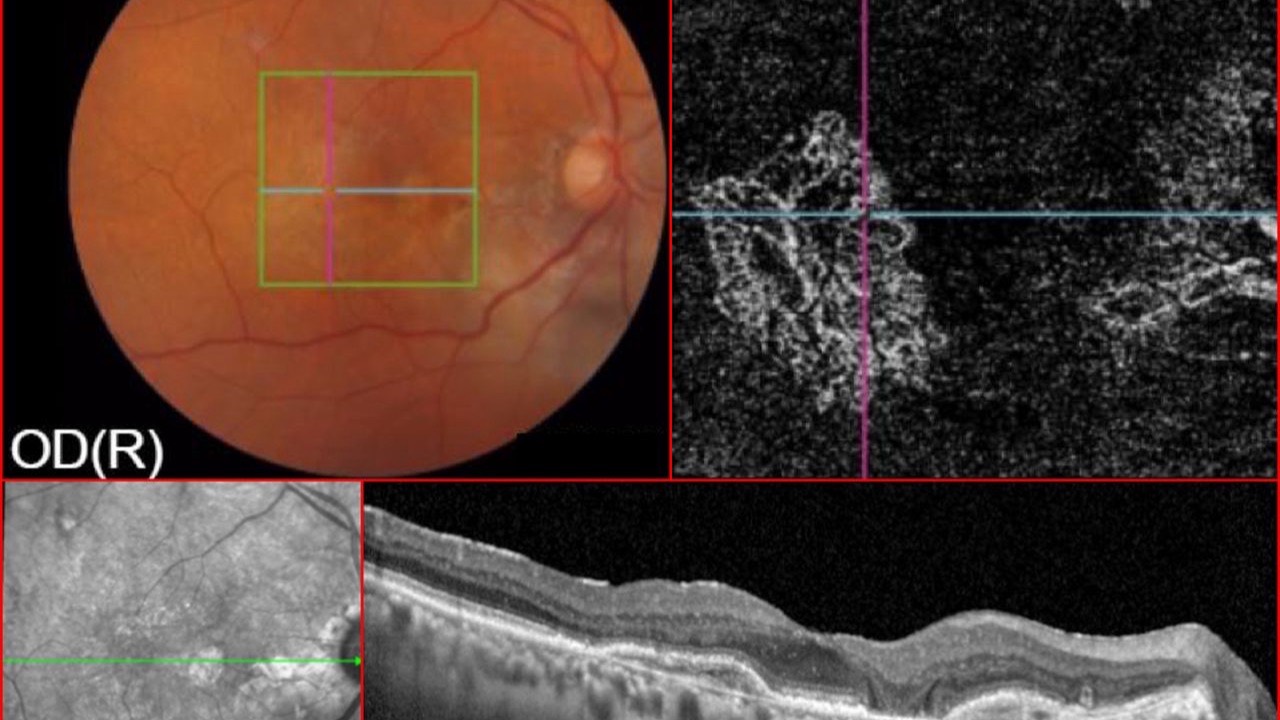

Nitric Oxide, OCTA & Glaucoma

NO3 via Vyzulta (latanoprostene bunod) may just matter.

A recent investigation was published regarding the impact of latanoprostene bunod on optical coherence tomography angiography (OCT-A) parameters in newly diagnosed open-angle glaucoma patients.

Changes in both vessel density and intraocular...